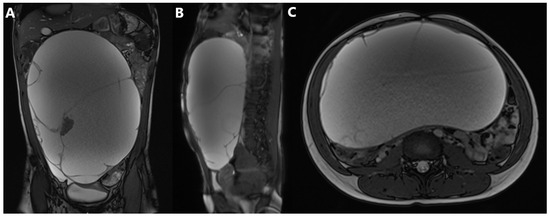

Background: Collision tumors, especially in the ovary, are a rare phenomenon where two distinct types of tumors develop adjacent to each other within the same organ but remain separate histologically. We present a case of the first collision ovarian tumor in a [...] Read more.

Background: Collision tumors, especially in the ovary, are a rare phenomenon where two distinct types of tumors develop adjacent to each other within the same organ but remain separate histologically. We present a case of the first collision ovarian tumor in a 14-year-old girl consisting of a combined tumor and a mature teratoma. Case Report: A 14-year-old girl presented with abdominal swelling for the past three months, without other symptoms. Ultrasound (US) examination of the abdomen revealed a large cystic mass with multiple septa, filling the entire abdomen from the diaphragm to the pelvis. Magnetic resonance imaging (MRI) showed an intraperitoneal mass, inseparable from the right ovary, measuring 22 cm × 13 cm × 30 cm. Serum tumor markers were within normal limits. The tumor mass was completely extirpated along with the fallopian tube. Histological and immunohistochemical analysis determined that it was a mucinous cystadenocarcinoma, characterized by a transition pattern from benign and borderline components to an adenocarcinoma component with a smaller mature teratoma. Six-month follow-up revealed no recurrence or postoperative complications. Conclusions: As the first documented case, this case provides valuable insights into pediatric ovarian neoplasms, guiding future diagnostic and therapeutic approaches. Full article

Show Figures

Figure 1